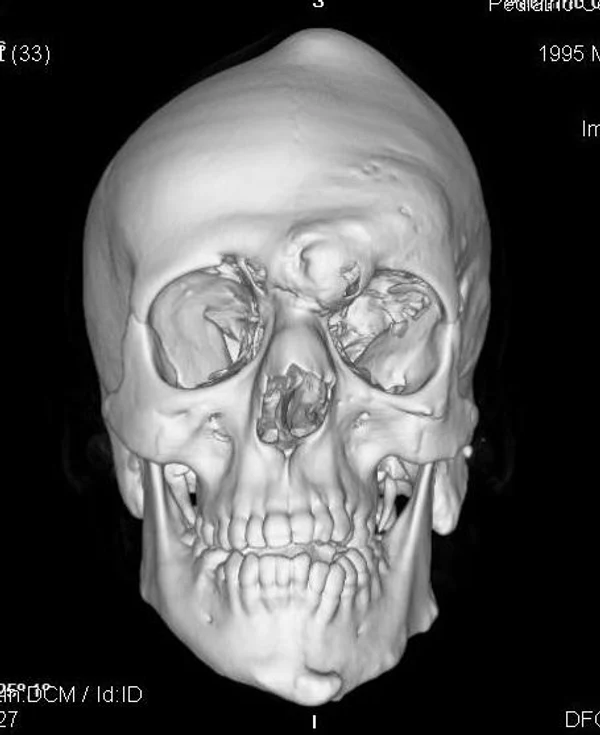

Удаление опухолей черепаВ качестве примера лечения пациентов с опухолями черепа привожу личное наблюдение пациента грудного возраста с опухолью черепа. В возрасте 1 мес. у ребёнка в затылочной области слева родителями обнаружено плотное образование диаметром 5 мм. За 3 мес. до госпитализации образование значительно увеличилось в размерах. При поступлении в возрасте 6 мес. в затылочной области слева (в проекции лямбдовидного шва) имеется безболезненное, плотное, неподвижное, бугристое образование размерами 5 х 4 х 2 см. При КТ и МРТ головы выявлена опухоль черепа в области астериона слева, обладающая преимущественно интракраниальным ростом (рис. 30 а). Ребёнку выполнено удаление опухоли черепа (рис. 30 б). Образовавшийся дефект черепа больших размеров закрыт перфорированной титановой пластиной (рис. 30 в). При наблюдении пациента в течении 2-х лет рецидива заболевания и деформации черепа не отмечалось.